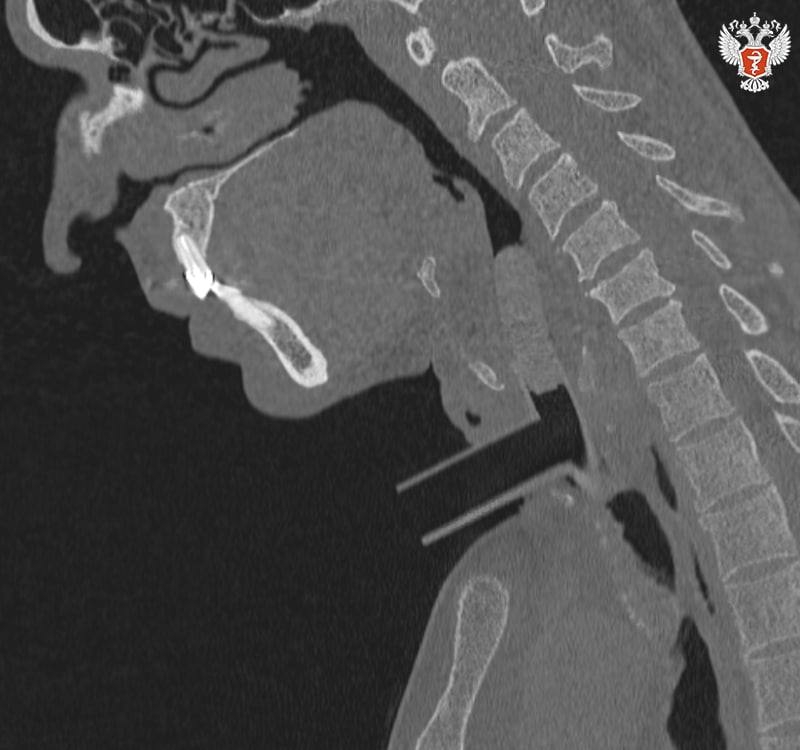

Специалисты Пироговского Университета Минздрава России и НИКИО им. Л.И. Свержевского представили новую систему анатомически адаптированных силиконовых стентов и комплексную тактику лечения хронического рубцового стеноза гортани и трахеи.

💡 Хронический рубцовый стеноз гортани и трахеи — тяжелое заболевание, при котором возникает стойкое сужение просвета дыхательных путей вследствие разрастания плотной соединительной ткани, которое приводит к развитию дыхательной недостаточности.

🔴 анатомически адаптированные стенты точно повторяют контуры дыхательных путей, обеспечивая стабильный просвет и минимизируя травму;